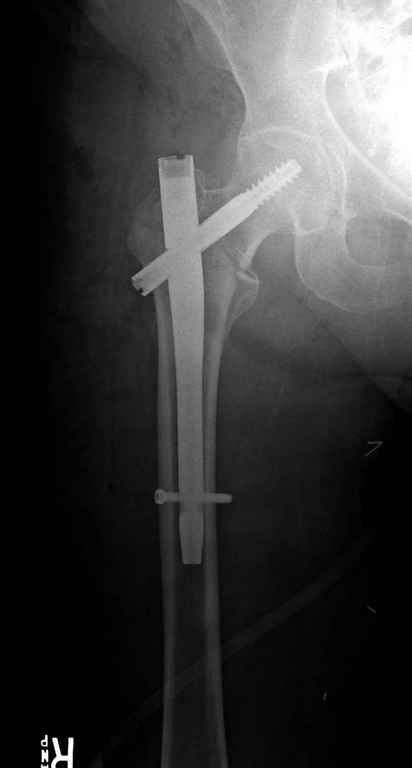

Перелом тут больше подвертельный. Нагрузка без торцевого упора на уровне перелома привела к телескопированию отломков на стержне. Ну и варус небольшой тоже свою лепту внес - если бы его не было, контактирующие латеральные стенки обоих отломков предотвратили бы укорочение, да и срослось бы за пару месяцев. А раз не срослось, упора отломков нет, более слабым местом оказались не нижние винты, а кость в головке и шейке. Так что надо было хотя бы удалить нижние винты до начала полной нагрузки.

Наверно, эндопротезирование. Есть более щадящий вариант - реостеосинтез (с устранением варуса и укорочения!), а после сращения и при наличии выраженного болевого синдрома - стандартное протезирование.

На мой взгляд, причиной телескопирования явилось несоответствие диаметра гамма нэйл с диаметром канала подвертельного отдела бедра: обратите внимание на величину протрузии шеечного винта и величину медиализации дистального фрагмента - они одинаковы, смещение или телескопирование фрагментов происходило до того момента, пока гамма нэйл не упёрся в медиальный кортекс и образовалось пространство между латеральным

кортексом и латеральной поверхностью гвоздя.

Диаметр гаммы в диафизарной части ~11 мм. А диаметр канала, тем более у пожилых с остеопорозом, может быть мм 15. Даже рассверливать обычно не приходится, после формирования широкого канала в вертельной области можно сразу толкать гвоздь, он влетает, как карандаш в стакан. Так что соответствия диаметров не бывает никогда. Однако представленная ситуация случается далеко не каждый раз. Если гвоздь в центральном отломке входит чуть медиальнее верхушки вертела, и идет вдоль передне-латеральной стенки центрального отломка, то все будет хорошо.

В приложении похожий пример, к счастью, пациентка появилась не после, а "за полчаса" до протрузии. Пересинтезировали с исправлением ошибок.

В данном случае в головке бедра и в вертлужной впадине огромный дефект, навряд ли удалением импланта или заменой на другой можно сохранить сустав.

Вашему вниманию представляется похожий случай, пациентке 70, осложнился в течение одного месяца после операции. Ревизия с заменой сустава, кабельная фиксация на трохантер. При установке в дистальном диафизе обнаружен тонкий кортикальный слой и сделана профилактика от возможного перелома аллографтом.